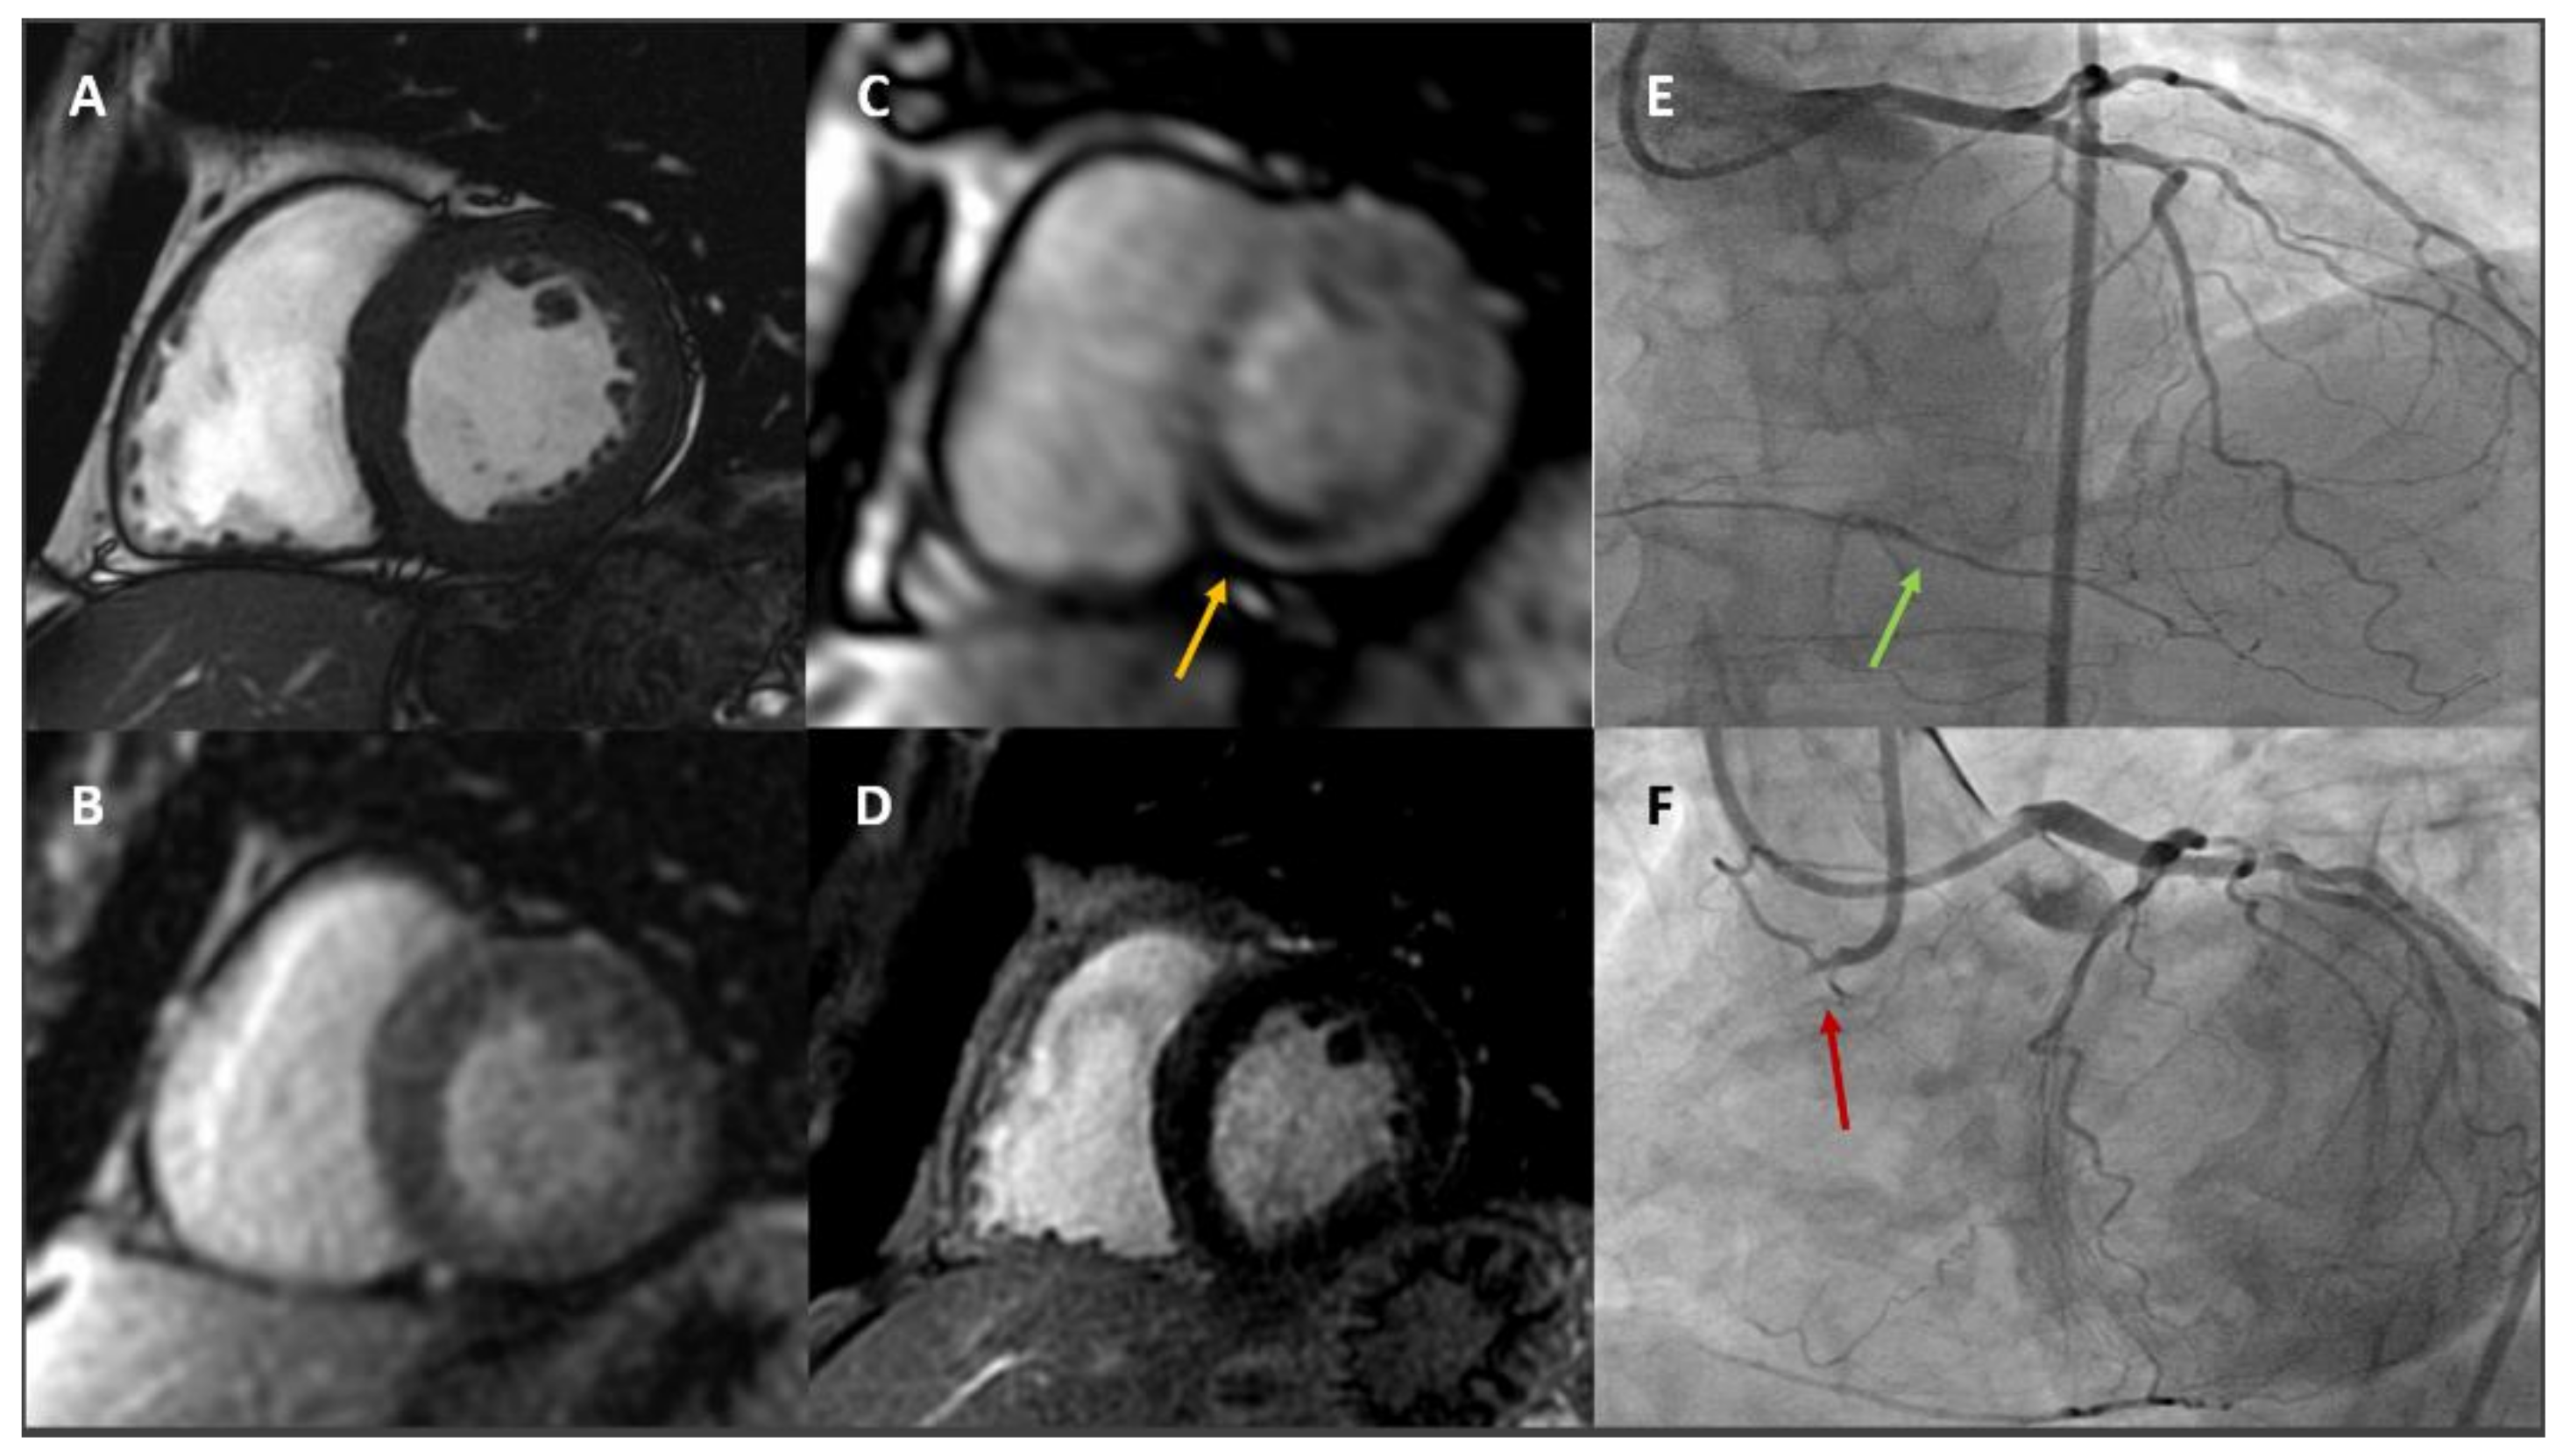

- Coelho-Filho, O.R.; Rickers, C.; Kwong, R.Y.; Jerosch-Herold, M. MR myocardial perfusion imaging. Radiology 2013, 266, 701–715. [Google Scholar] [CrossRef]

- Nagel, E.; Greenwood, J.P.; McCann, G.P.; Bettencourt, N.; Shah, A.M.; Hussain, S.T.; Perera, D.; Plein, S.; Bucciarelli-Ducci, C.; Paul, M.; et al. Magnetic Resonance Perfusion or Fractional Flow Reserve in Coronary Disease. N. Engl. J. Med. 2019, 380, 2418–2428. [Google Scholar] [CrossRef]

- Baritussio, A.; Scatteia, A.; Dellegrottaglie, S.; Bucciarelli-Ducci, C. Evidence and Applicability of Stress Cardiovascular Magnetic Resonance in Detecting Coronary Artery Disease: State of the Art. J. Clin. Med. 2021, 10, 3279. [Google Scholar] [CrossRef] [PubMed]

- Baessato, F.; Guglielmo, M.; Muscogiuri, G.; Baggiano, A.; Fusini, L.; Scafuri, S.; Babbaro, M.; Mollace, R.; Collevecchio, A.; Guaricci, A.I.; et al. Stress CMR in Known or Suspected CAD: Diagnostic and Prognostic Role. Biomed. Res. Int. 2021, 2021, 6678029. [Google Scholar] [CrossRef]

- Pontone, G.; Andreini, D.; Bertella, E.; Loguercio, M.; Guglielmo, M.; Baggiano, A.; Aquaro, G.D.; Mushtaq, S.; Salerni, S.; Gripari, P.; et al. Prognostic value of dipyridamole stress cardiac magnetic resonance in patients with known or suspected coronary artery disease: A mid-term follow-up study. Eur. Radiol. 2016, 26, 2155–2165. [Google Scholar] [CrossRef]

- Antiochos, P.; Ge, Y.; Heydari, B.; Steel, K.; Bingham, S.; Abdullah, S.M.; Mikolich, J.R.; Arai, A.E.; Bandettini, W.P.; Patel, A.R.; et al. Prognostic Value of Stress Cardiac Magnetic Resonance in Patients With Known Coronary Artery Disease. JACC Cardiovasc. Imaging 2021, 15, 60–71. [Google Scholar] [CrossRef]

- Heidary, S.; Patel, H.; Chung, J.; Yokota, H.; Gupta, S.N.; Bennett, M.V.; Katikireddy, C.; Nguyen, P.; Pauly, J.M.; Terashima, M.; et al. Quantitative tissue characterization of infarct core and border zone in patients with ischemic cardiomyopathy by magnetic resonance is associated with future cardiovascular events. J. Am. Coll. Cardiol. 2010, 55, 2762–2768. [Google Scholar] [CrossRef] [PubMed] [Green Version]

- Kwong, R.Y.; Ge, Y.; Steel, K.; Bingham, S.; Abdullah, S.; Fujikura, K.; Wang, W.; Pandya, A.; Chen, Y.Y.; Mikolich, J.R.; et al. Cardiac Magnetic Resonance Stress Perfusion Imaging for Evaluation of Patients With Chest Pain. J. Am. Coll. Cardiol. 2019, 74, 1741–1755. [Google Scholar] [CrossRef]

- Kotecha, T.; Chacko, L.; Chehab, O.; O’Reilly, N.; Martinez-Naharro, A.; Lazari, J.; Knott, K.D.; Brown, J.; Knight, D.; Muthurangu, V.; et al. Assessment of Multivessel Coronary Artery Disease Using Cardiovascular Magnetic Resonance Pixelwise Quantitative Perfusion Mapping. JACC Cardiovasc. Imaging 2020, 13, 2546–2557. [Google Scholar] [CrossRef] [PubMed]

- Kotecha, T.; Monteagudo, J.M.; Martinez-Naharro, A.; Chacko, L.; Brown, J.; Knight, D.; Knott, K.D.; Hawkins, P.; Moon, J.C.; Plein, S.; et al. Quantitative cardiovascular magnetic resonance myocardial perfusion mapping to assess hyperaemic response to adenosine stress. Eur. Heart J. Cardiovasc. Imaging 2021, 22, 273–281. [Google Scholar] [CrossRef]